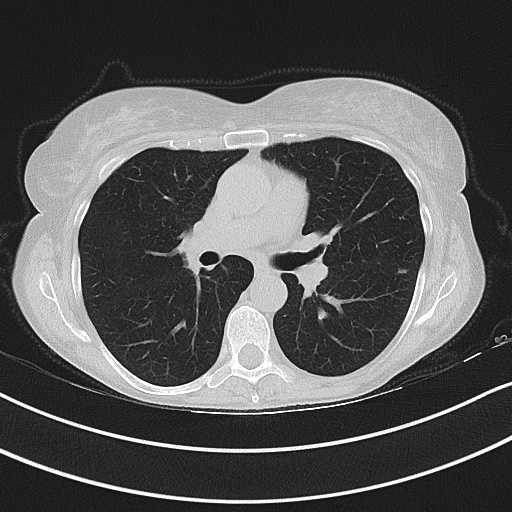

Figure 3 illustrates this further. It presents three cases of unsegmented slices of a CT scan (left column), along with their cases when they are segmented with conventional approaches (middle column) and with our proposed framework SAM2CLIP2SAM (right column). It is evident that the segmentation result with our approach is more accurate and error-prune. In the first case (top row), the mediastinal mass between the left and right lungs is kept when the slices are segmented with conventional approaches, whereas it is not kept (i.e., it is black) when the slices are segmented with our SAM2CLIP2SAM framework. In all cases, one can also note that a bit of the pleural space (e.g. on the peripheral of the lungs) is also kept and is not masked when the slices are segmented with conventional approaches; this is not the case when the slices are segmented with our SAM2CLIP2SAM framework.

Original-Unsegmented Conventionally segmented SAM2CLIP2SAM segmented